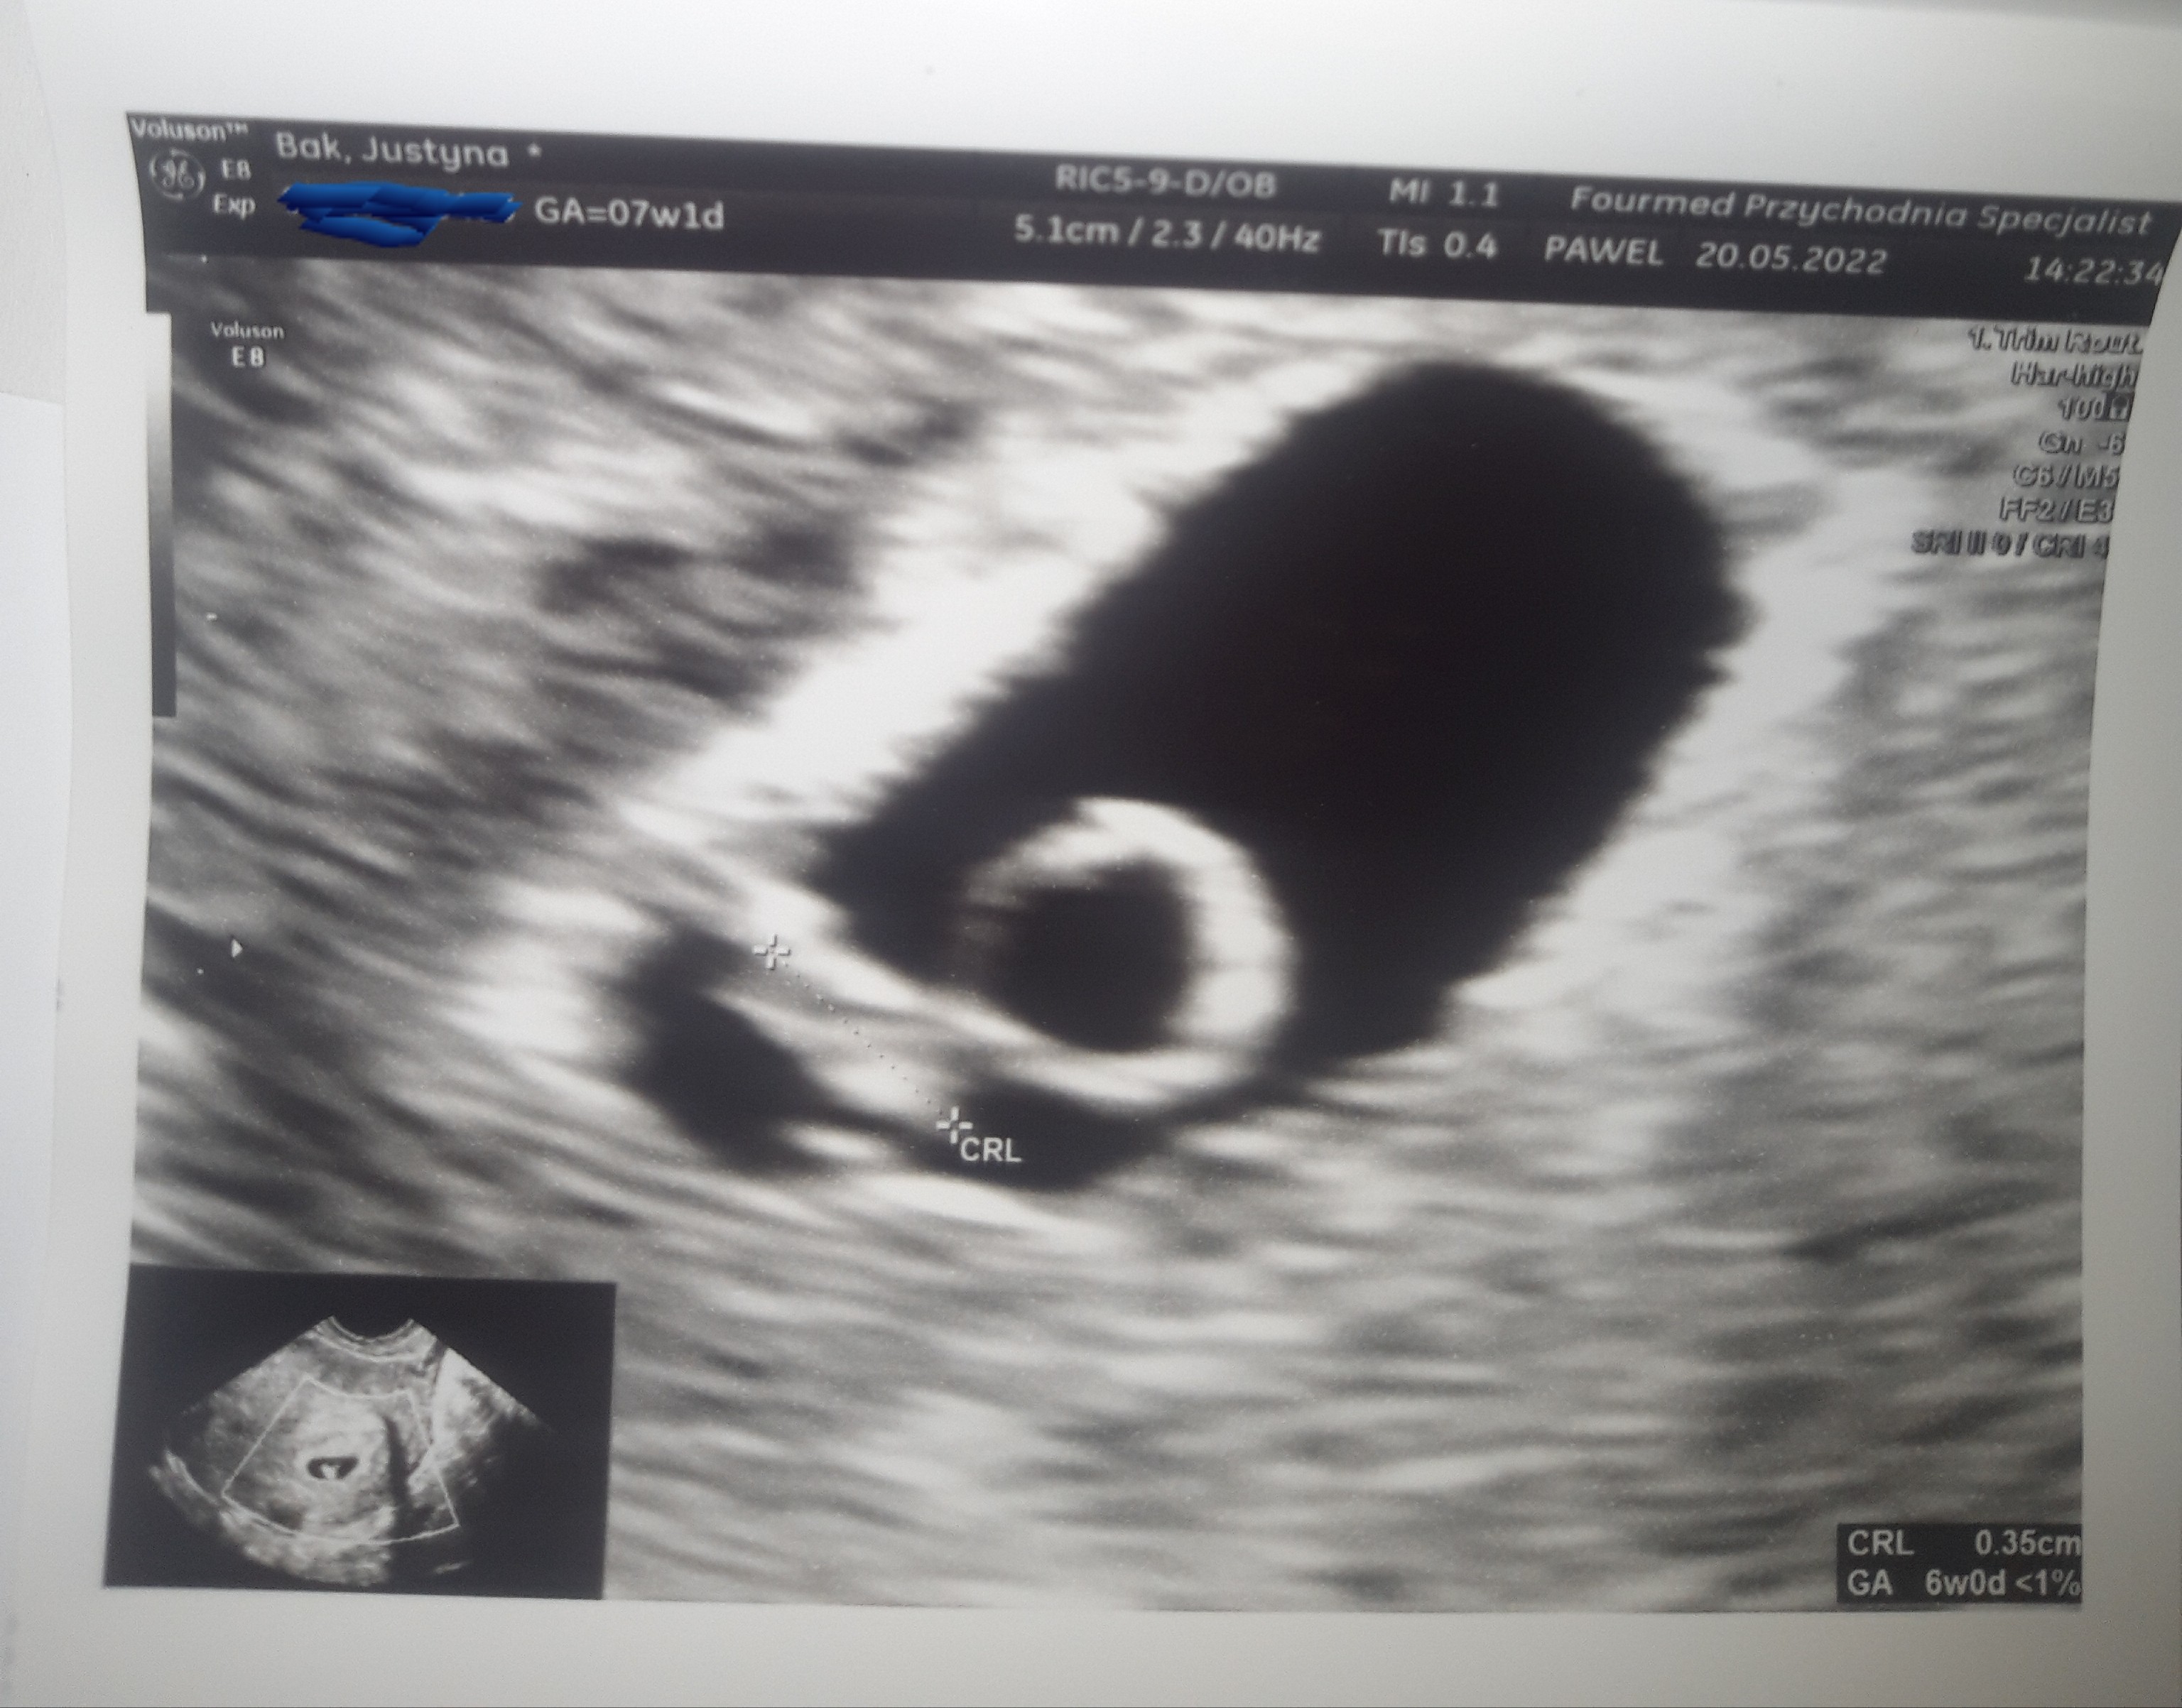

Jest zarodek ma 3,5 mm, wiec malusie to moje szczęście! Serduszko bije, nie usłyszałam jego bicia ale widziałam na monitorze jak ładnie pracuje (taka pulsująca kropeczka).

Z OM wychodzi 7 tydz+ 1 dzień, a z USG 6 tydzień 0 dni.